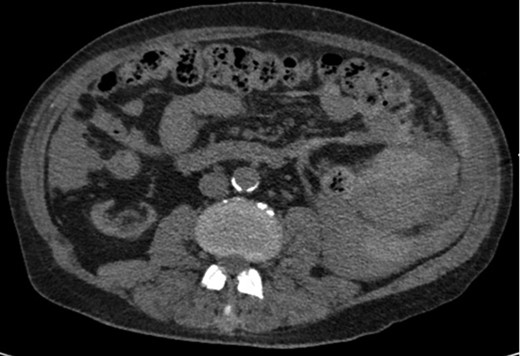

A 68-year-old male with history of living donor renal transplant presented to the ED with acute onset of profound weakness, fatigue, left upper quadrant abdominal pain, hypotension and lactic acidosis. On exam, he exhibited mild left upper quadrant and epigastric tenderness without evidence of peritonitis. CT imaging demonstrated splenomegaly with a large splenic hematoma measuring 15.7 × 9.2 × 12 cm and associated hemoperitoneum (Figs 1–3). In addition, innumerable osseous lytic lesions were identified. Given these findings, emergent surgical consultation was obtained and his coagulopathy reversed. He remained hypotensive despite resuscitation, thus was taken for laparotomy. Upon abdominal entry, a large amount of old clot was evacuated. The abdomen was packed in all quadrants in the standard fashion. Upon removal of the left upper quadrant packs, active hemorrhage began to well from the region of the spleen which was mobilized and removed via splenectomy. Upon gross inspection, the spleen was hyperemic and abnormally indurated, with an avulsion type injury extending several centimeters across the inferior pole. There was no evidence of pseudoaneurysm or other gross pathology. Given the patient was mildly hypothermic and coagulopathic with continued oozing from the retroperitoneum, the decision was made to pack the splenic fossa and place a temporary wound vac. The patient was transported to the ICU for resuscitation and brought back to the OR the next morning for re-exploration and closure. Despite hemodynamic stabilization, he underwent a prolonged hospitalization complicated by atrial fibrillation, renal allograft failure, VAP, and ultimately PEA arrest progressing to asystole. He died 6 weeks following splenectomy. The pathology from the spleen revealed splenomegaly with parenchyma that was replaced with amorphous and acellular eosinophilic material. Histologic staining (Thioflavin-T) was positive for amyloidosis, AL-type. Oncology was consulted based on these findings with concern for lymphoproliferative disorder given osseous findings on CT, splenic pathology, and history of immunosuppression. Bone marrow biopsy was subsequently obtained which showed more than 50% atypical plasma cells/plasma blasts (CD138+; PAX5 negative; EBV (EBER) negative) and no amyloidosis, consistent with multiple myeloma. Urine showed Bence-Jones protein. Serum immunofixation studies were remarkable for a monoclonal IgG lambda gammopathy, consistent with the diagnosis of AL amyloidosis associated with systemic myeloma.

Axial CT imaging showing hemoperitoneum secondary to splenic rupture.